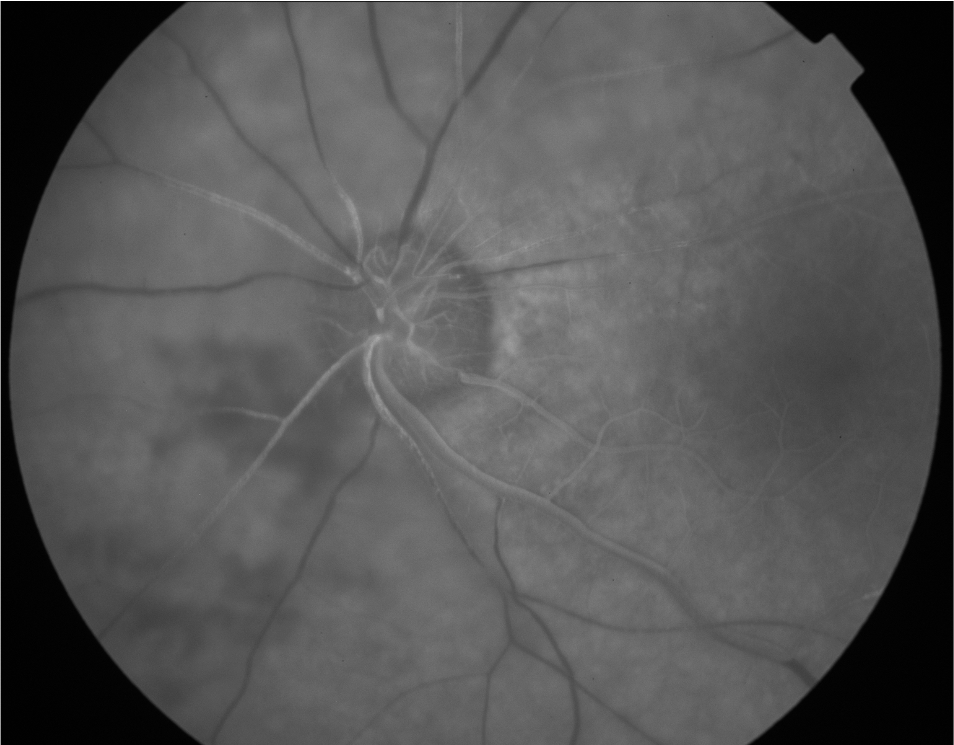

Hypofluorescence Case #2

ID: 72M

Reason for Referral: Sudden painless vision loss in the right eye. No trauma.

Past Medical History: Hypertension (10 yrs, poorly controlled), Hyperlipidemia, Type 2 Diabetes (HbA1c 8.8%).

• VA NLP OD, 20/40 OS

• RAPD present in OD, PEARRLA

• Vascular Filling Defect Due to CRAO

A filling defect causes hypofluorescence due to reduced perfusion - meaning less fluorescein is reaching the vasculature.

• Arterial Defect